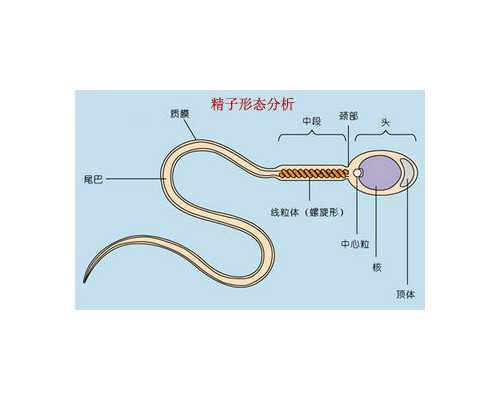

溫馨提示

取卵前打hcg的作用是為了促進(jìn)卵泡進(jìn)行排卵,HCG的主要作用就是誘發(fā)成熟卵泡中的卵母細(xì)胞最后成熟,而HCG在正確的時(shí)機(jī)使用才能獲得理想的治療效果,一般是在卵泡達(dá)到18mm左右停用促排藥物,在最后一次藥物使用后的36小時(shí)左右注射HCG,HCG注射后36-37小時(shí)內(nèi)完成取卵手術(shù)。